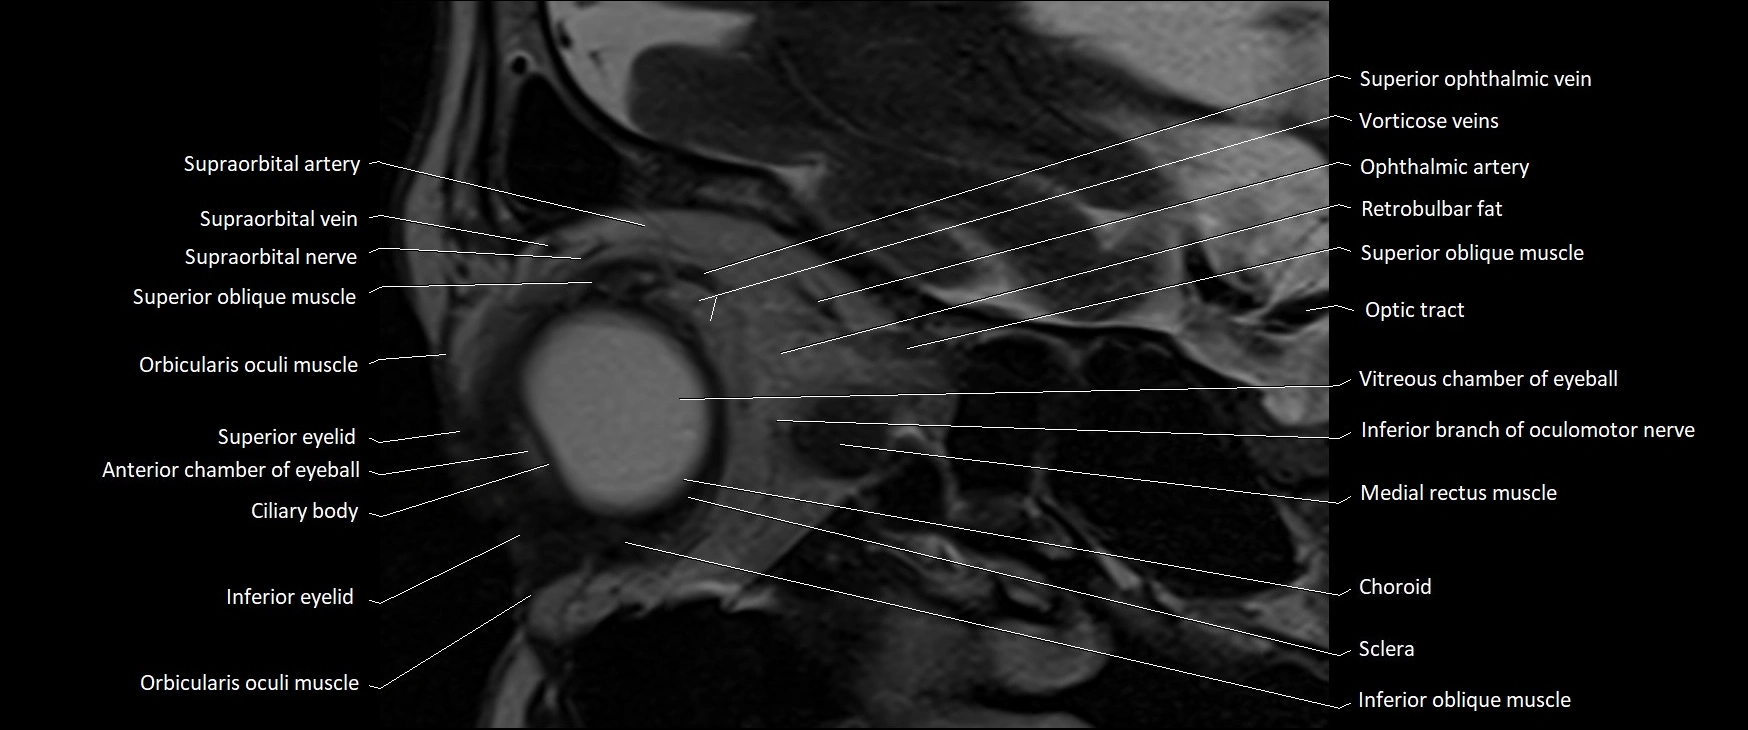

MRI images